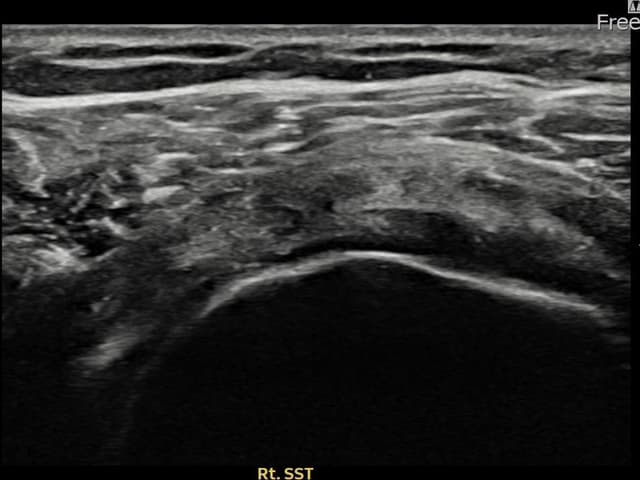

[촬영시기:24.10.14~24.12.23]

[어깨인대 축소봉합술] 우측 어깨 통증으로 팔을 올리기 어려웠으며, 충격파 치료에 반응이 없어 내원하셨습니다.